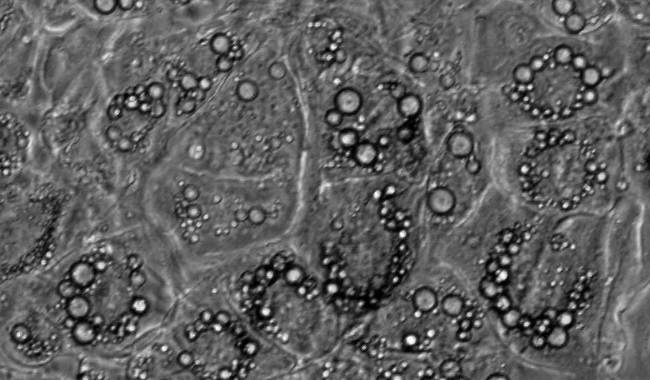

脂滴計數(shù)圖像分析

脂滴是調節(jié)中性脂質儲存的基礎,可以根據(jù)脂滴研究代謝的需求。但它們不僅是能量庫,因為這種動態(tài)的細胞器是許多生物過程的一部分,如細胞能量平衡和脂質代謝。脂滴法在代謝性疾病的研究,如肥胖、糖尿病和動脈粥樣硬化有重要的作用。

脂滴個數(shù)

脂滴覆蓋面積

平均覆蓋面積

區(qū)間分布

單個細胞的脂滴個數(shù)和覆蓋面積